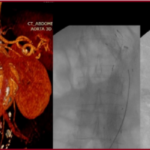

Ανεύρυσμα κοιλιακής αορτής: Mε stent-graft

Η ενδαγγειακή αποκατάσταση ανευρύσματος κοιλιακής αορτής με stent-graft είναι ελάχιστα επεμβατική μέθοδος κατά την οποία τοποθετείται ειδικό ενδομόσχευμα στην αορτή για την απομόνωση του ανευρύσματος.